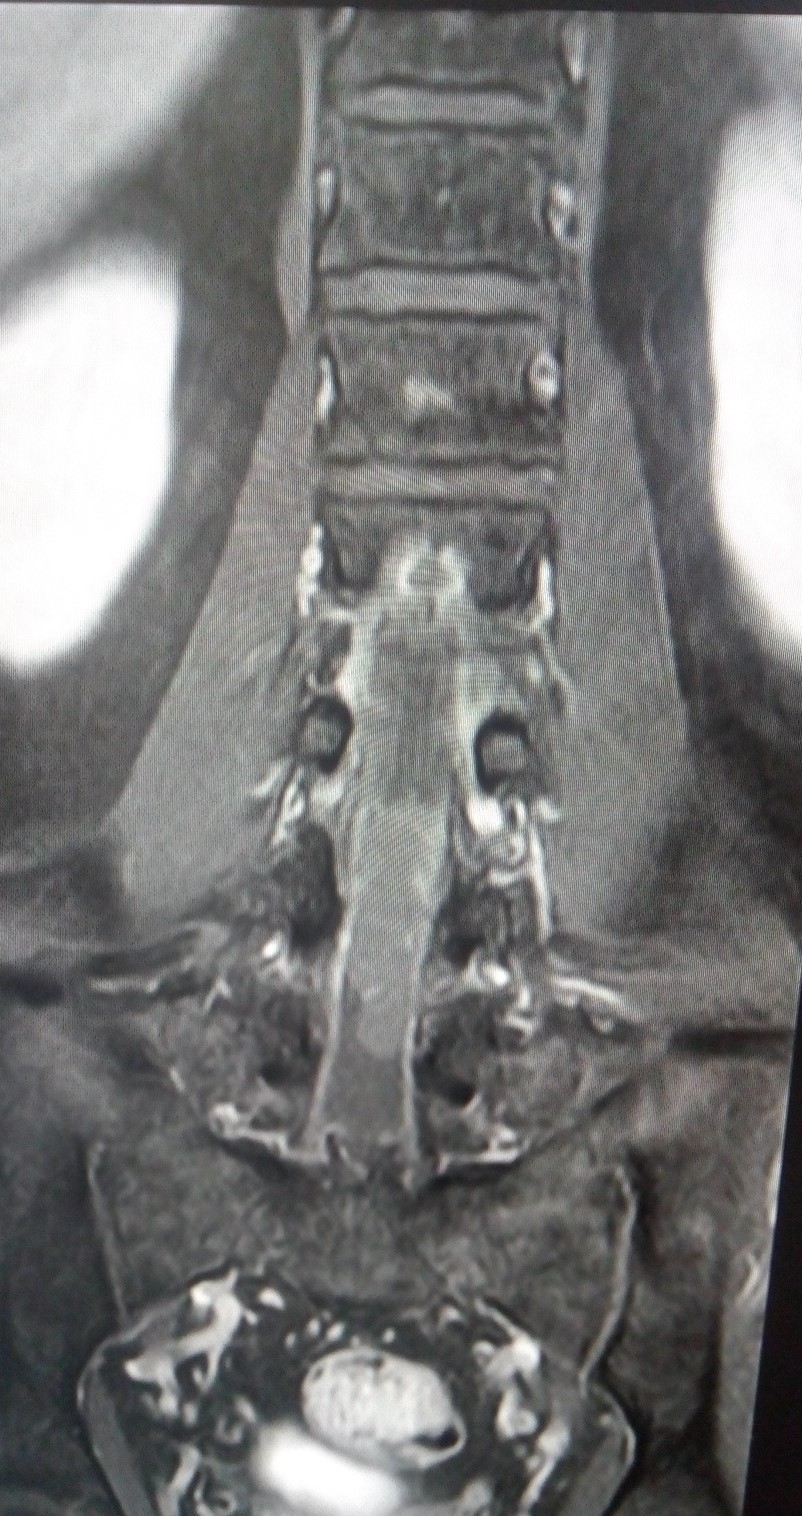

Cauda equina mass An Approach Sumer's Radiology Blog